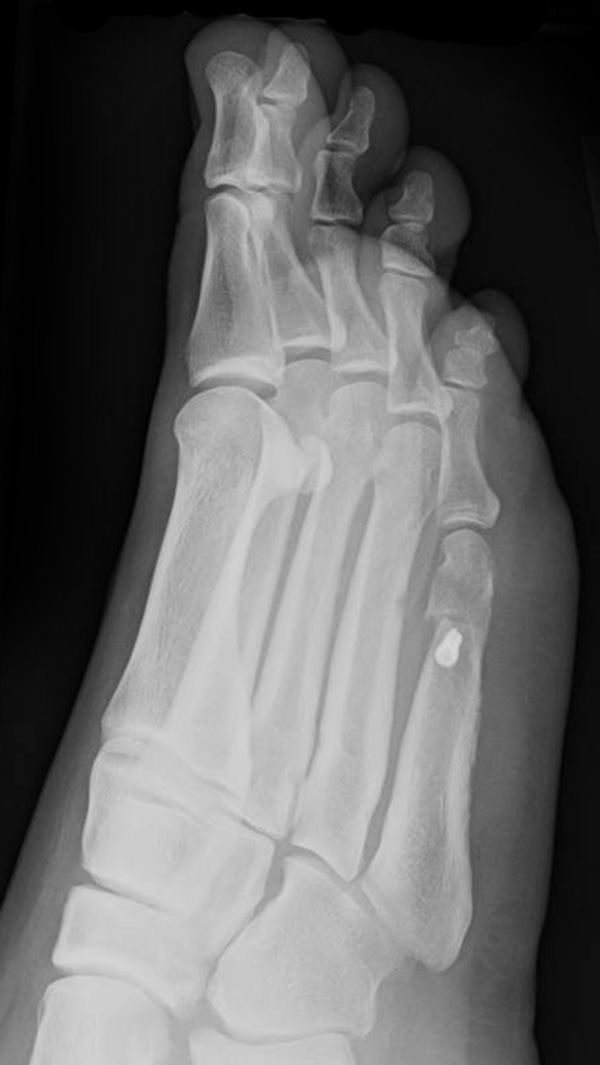

Abb. 12a: Typ III Deformität präoperativ im belasteten dp Röntgenbild.

Abb. 12b: Dorsoplantare Röntgenkontrolle nach medial schließender Osteotomie mit Schraubenosteosynthese.

Abb. 12c: Schrägaufnahme nach medial schließender Osteotomie mit Schraubenosteosynthese.

Abb. 12d: Seitliche Aufnahme nach medial schließender Osteotomie mit Schraubenosteosynthese.